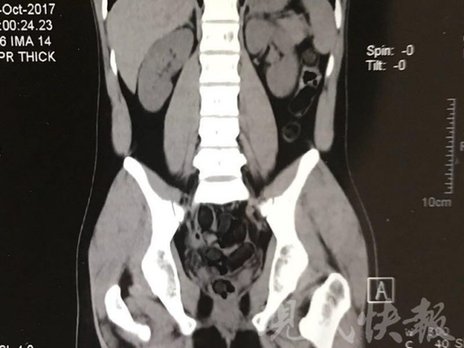

小伙體內(nèi)藏毒300余克 CT掃描圖密密麻麻

運毒小伙:希望被判處死刑

由于毒品在體內(nèi)一旦泄露有可能致命,警方第一時間將阿永帶到醫(yī)院進(jìn)行檢查。CT 掃描的結(jié)果顯示,阿永體內(nèi)布滿了密密麻麻的白色圓柱狀固體,就像一粒粒的蠶蛹。在南京市公安局鼓樓分局二板橋派出所,阿永分四次排出了毒品,毛重369.99克。經(jīng)訊問,阿永交代了自己全部的犯罪事實。目前,阿永已被刑事拘留。